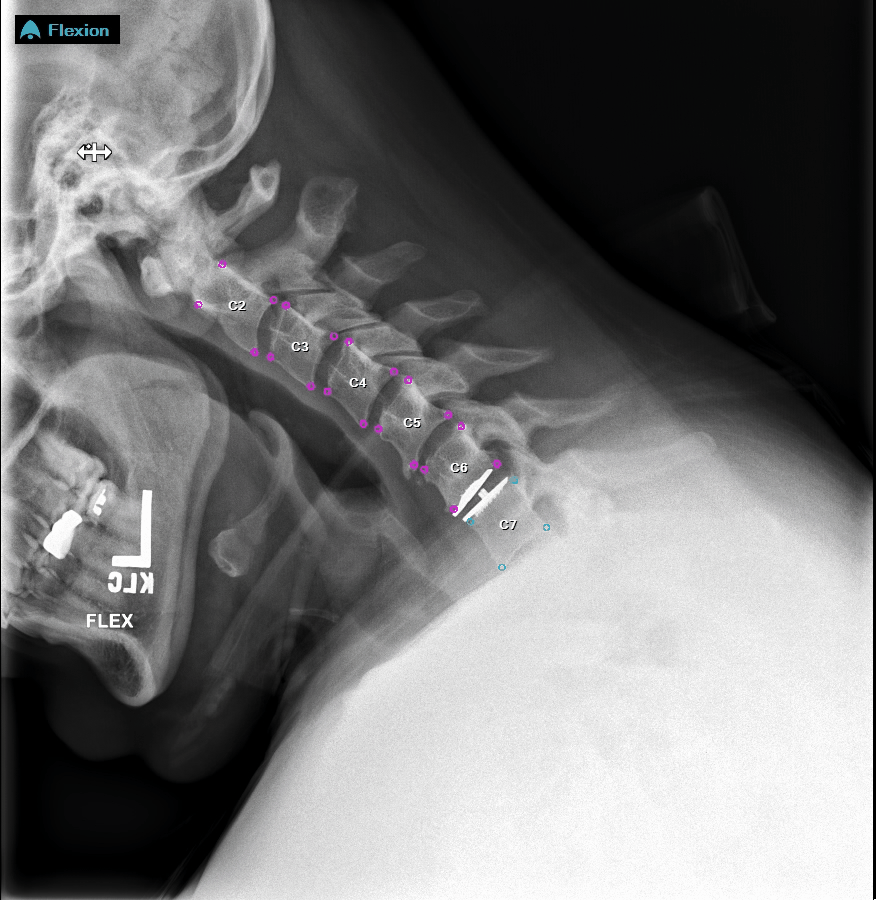

HOUSTON, TX, UNITED STATES, February 18, 2025 /EINPresswire.com/ -- Medical Metrics Diagnostics, Inc. (“MMDx” or the “Company”), a global leader in spine image analysis solutions and services, is excited to announce its participation at the upcoming Spine Summit Meeting in Tampa, FL, 2/20 – 2/23, 2025. MMDx will be showcasing SpineCAMP™, the Company’s FDA cleared Software as a Medical Device (SaMD) at its booth, #217. SpineCAMP is a fully-automated AI-powered solution that analyzes radiographs (X-ray images) of the spine to generate quantitative metrics and enhanced visualizations that are intended to support and augment clinical decision making. SpineCAMP is designed to seamlessly inject analysis results into imaging workflows within the clinician’s image viewing infrastructure and is commercially available via SaaS subscription.SpineCAMP driven research will be featured during Spine Summit in multiple e-posters and presentations that span a spectrum of topics including:

"We are excited to connect with meeting attendees in Tampa, and to demonstrate our imaging informatics capabilities" said Dennis Farrell, Chief Commercial Officer at MMDx. "We look forward to sharing how the precision metrics provided by SpineCAMP can aid physicians and other healthcare professionals in their assessment of spinal instability, alignment, fusion, motion preservation, and implant performance. We have a growing number of sites that are using the technology, and feedback is very positive. We are thrilled by the reception.”

Trevor Grieco, PhD, Director of Medical Device Solutions for MMDx added, “As everyone attending this meeting appreciates, the spine is a beautifully complex biomechanical system that enables upright posture, controlled motion, and serves to protect key elements of the nervous system. For years, we have been working to democratize access to the precision measurement tools that can be used at the point of care to assess the biomechanical integrity of the spine in a patient specific manner. SpineCAMP is the culmination of this work and we are excited to demonstrate it’s clinical and research utility at the upcoming Spine Summit.”

According to Sigurd Berven, MD, Professor of Orthopedic Surgery at UCSF, “SpineCAMP provides an automated measurement of the critical parameters that are required to make informed decisions regarding reconstructive surgery. In addition to enhancing speed of measurements, it has demonstrated accuracy and reproducibility that is superior to manual measurements of the radiographic parameters that we already make. Using our existing infrastructure, we are able to get instantaneous radiographic measurements for static and dynamic parameters.”